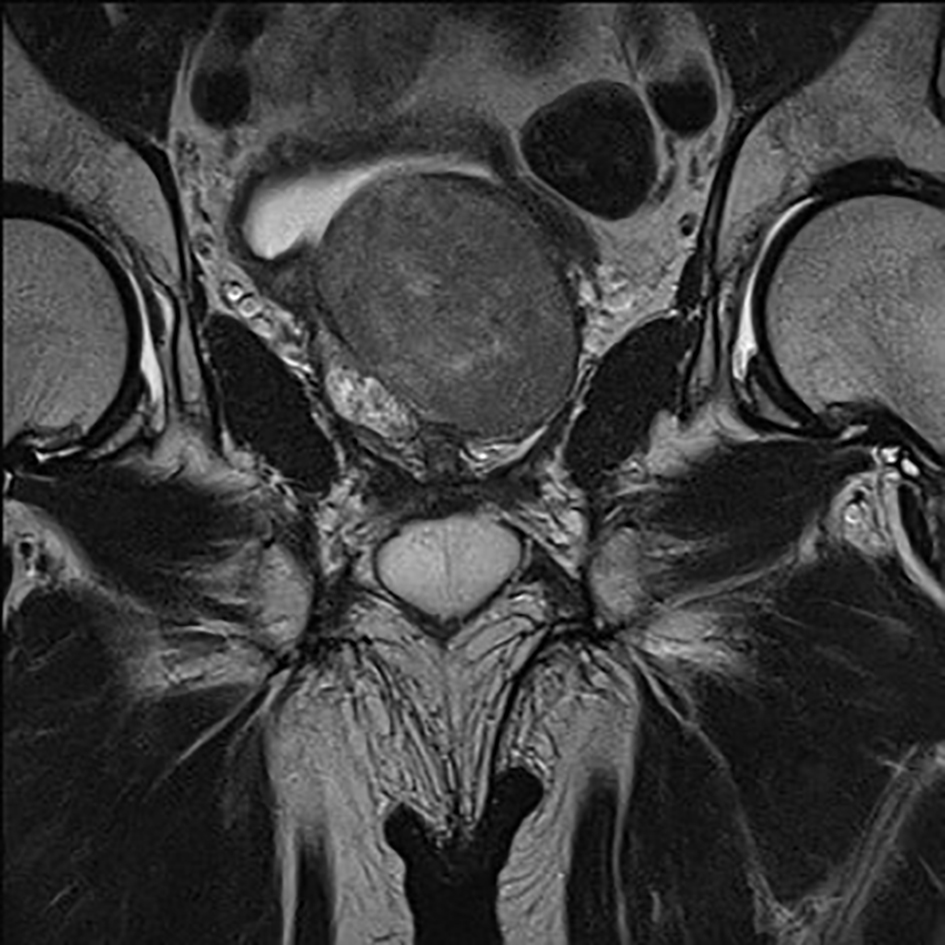

Primary histopathological examination based on prostatic tissue attained from the TUR-P procedure demonstrated prostatic leiomyoma. The patient was then referred for further urological evaluation at the Department of Urology, Rigshospitalet. At the first visit to our outpatient clinic, PSA was normal (2.7 ng/mL, ratio 0.36). A transrectal ultrasonography showed an 80 cc prostate with an isoechoic signal. Subsequent prostatic biopsies and revision of the primary specimen revealed a smooth muscle tumor with increased cellularity, large cells with frequent bizarre forms. Nuclei were pleomorphic and hyperchromatic and there were occasional typical mitotic figures (0-1/10 high power field). Scattered multinucleated tumor giant cells and few nuclei with pseudoinclusions were seen. There was no necrosis or hemorrhage (Figs. 1 and 2). The primary diagnosis was thus confirmed, and no prostatic malignancy was demonstrated. A CT scan showed no signs of metastasis. An MRI showed a 5 × 6 × 6 cm tumor of the prostate with apparent focal encasement of the right seminal vesicle, no enlarged lymph nodes or bony metastases were seen (Fig. 3). A PET-CT showed no signs of malignancy in the prostate. Liver enzymes normalized without intervention and no explanation of the previously elevated levels was found.

![]() Click for large image | Figure 3. MRI, ventral view. |